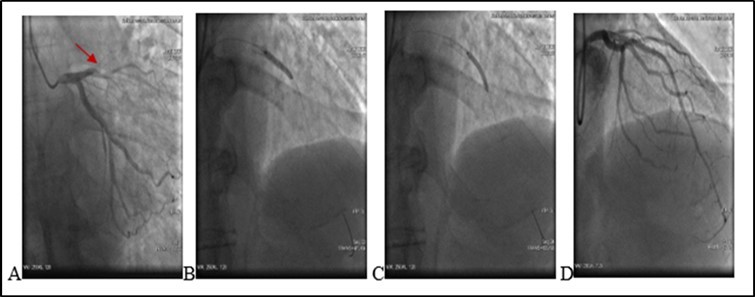

21.06.20 05:03 Am the patient complained chest pain. A drop in blood pressure and bradycardia was noted. T/A 80/60 mm Hg. There was no changes on echocardiography. No pericardial separation. No ST segment changes on ECG . Due to hemodynamic instability we decided to repeat a coronary angiography and it again revealed a medial segment stent thrombosis in LAD with multiple extravasations at proximal and medial segments Type III and II (see. Figure 3) -late perforation of coronary artery. At proximal segment pericardial hemorrhage provided pericardial hematoma with diameter 9-10 mm. At medial were visualized. During coronary angiography a patient’s condition deteriorated. Blood pressure dropped to T/A 60/40 mm Hg. A cardiac tamponade developed because of blood leak into pericardial space. A 3 mm balloon was inflated immediately in the site of rupture, with complete occlusion of vessel, stopping of a blood flow in the LAD and termination of extravasation into the pericardial space.

Figure 3.A. (21.06.2020) Second acute stent thrombosis and perforation Type III and II (red arrows) B. Balloon inflation in the site of rupture (red circle).

A. (21.06.2020) Second acute stent thrombosis and perforation Type III and II (red arrows) B. Balloon inflation in the site of rupture (red circle).

Deployment of covered stents was not purposeful due to highly suspected infection. A decision was made for urgent surgical treatment. A patient was urgently transferred to a cardiac operation theater surgical department with inflated balloon to eliminate a blood leakage in the pericardium. Ligating the coronary artery with removing stents, subsequent bypass grafting was performed, with removal of 500 ml of coagulated blood from the pericardial space. Post-surgery period remained stable. Leukocytes - 14.24 x10`3/μ L (N 4-10). A Pseudomonas Aeruginosa (multirresistent) - was positive after coronary wall tissue histomorphological examination. During hospitalization developed renal insufficiency.